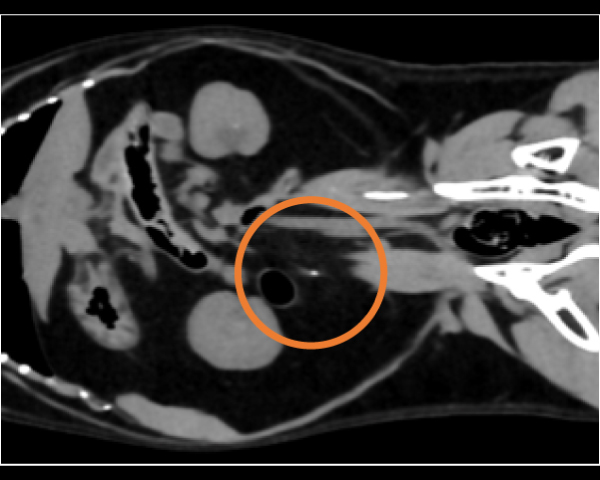

無麻酔CT検査にて結石の個数を確認

無麻酔CT検査にて異物の確定